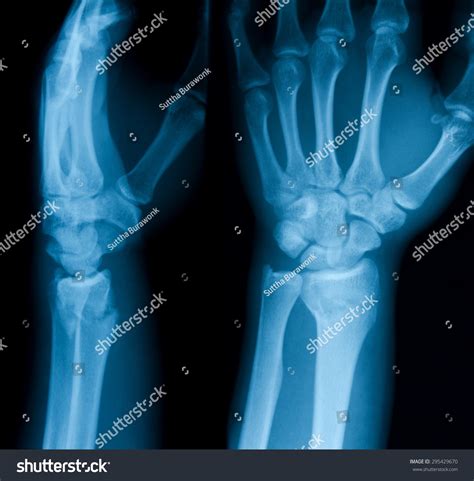

4. Multiple images are taken from different angles to provide a comprehensive view.

Interpreting a Normal Wrist Xray requires a trained eye. Radiologists look for several key features:

• Bone density and structure

• Alignment of the bones

• Presence of fractures or dislocations

• Signs of arthritis or other joint disorders

• Soft tissue abnormalities